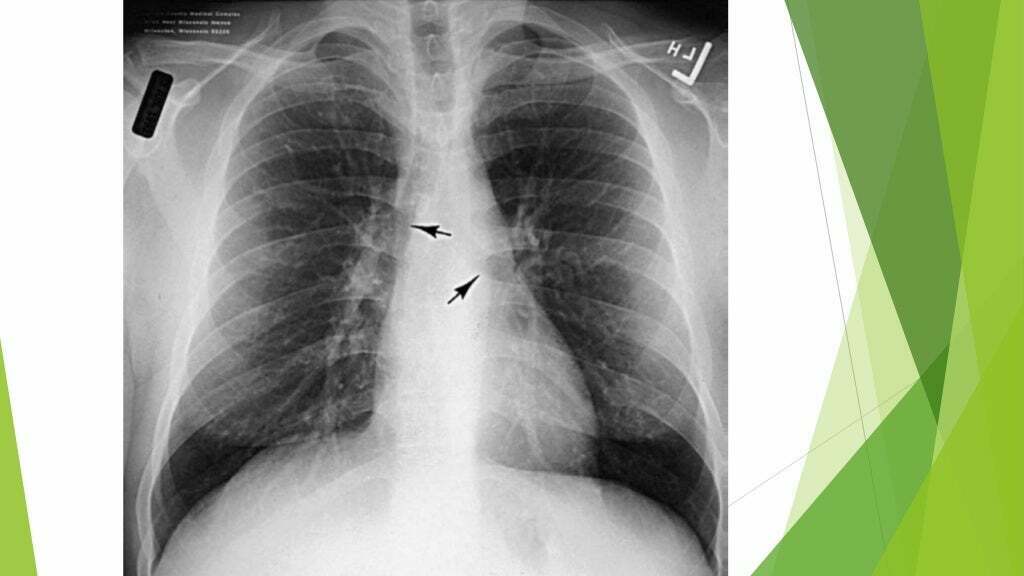

O que é o Sinal do Broncograma aéreo? Vias aéreas visíveis pela consolidação do pulmão (brônquios).

Qual sinal é esse? Sinal do broncograma aéreo

O que é o sinal do broncograma aéreo? Visibilidade das vias aéreas devido à consolidação do pulmão.